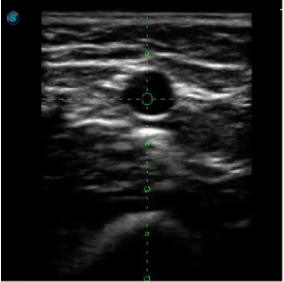

傳統(tǒng)腔內(nèi)探頭采用直柄設(shè)計,在搭配穿刺架使用時,手術(shù)空間小,不易操作;生殖專用的曲柄探頭,探頭柄采用彎曲成角度設(shè)計,可實(shí)現(xiàn)監(jiān)視、取卵兩不誤,搭載穿刺架時,可以清晰顯示穿刺針的進(jìn)針過程、深度和位置,實(shí)時監(jiān)視取卵全過程,保障取卵操作精準(zhǔn)與安全。

取卵臨床圖